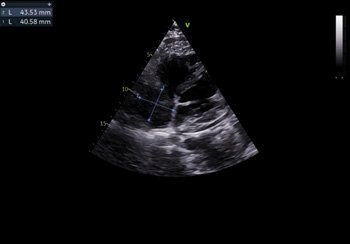

Management

After obtaining informed consent, the patient underwent onpump Coronary Artery Bypass Grafting (CABG) and Aortic Valve Replacement (AVR). He received a 19mm St. Jude mechanical valve and two grafts: a Saphenous Venous Graft (SVG) to the first Obtuse Marginal Branch (OM1) and another SVG to the distal RCA. Postoperatively, he was started on antiplatelets and anticoagulants with INR optimisation on day 1. His intercostal drain was removed on the 3rd postoperative day, and pacing wires were removed on the 9th postoperative day, with regular 2D ECHO monitoring. On the 9th postoperative day, a 2D ECHO showed a large collection in the anterior part of the Right Atrium (RA) causing inlet obstruction to the Right Ventricle (RV) in the form of functional Tricuspid Stenosis (TS) with a mean gradient of 6 mm Hg and right atrial tamponade (Figures 1,2).

Figure 1: Two-dimensional transthoracic echocardiographic subcostal four chamber view showing mass in the right atrium measuring 4.3 X 4.0cms.